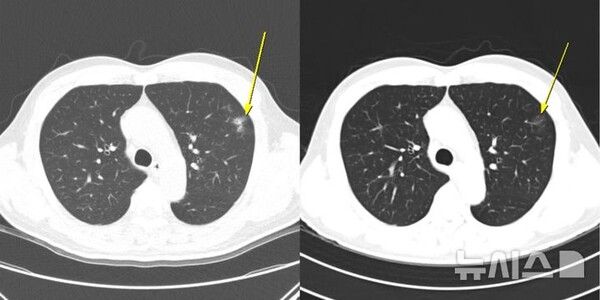

이에 연구팀은 치료 중 나타난 이상반응 양상에 따라 환자를 ▲이상반응이 전혀 없는 '무이상반응군' ▲임상 증상이나 혈액검사 이상을 동반한 '증상성 이상반응군'(증상군) ▲증상은 없지만 CT에서 폐 주변부 미세 염증성 음영, 일시적 대장벽 비후, 장간막 염증, 반응성 림프절 종대 등 면역반응으로 해석되는 변화만 나타난 '무증상 영상 이상반응군(무증상 영상군)'으로 분류했다. 전체 198명 중 무증상 영상군은 12명, 증상군은 56명, 무이상반응군은 130명이었다.

치료 반응률에서도 차이가 분명했다. 무증상 영상군의 객관적 반응률(ORR)은 41.7%, 질병조절률(DCR)은 100%로 가장 높았으며, 증상군은 각각 26.8%와 92.9%, 무이상반응군은 13.8%와 60.0%로 뒤를 이었다. 이는 환자가 증상을 느끼지 않더라도 CT에서 보이는 경미한 변화가 치료 반응이 좋은 환자를 조기에 식별하는 중요한 단서가 될 수 있음을 시사한다.

유수종 교수(소화기내과)는 "환자가 특별한 증상을 느끼지 않더라도 영상에서 나타나는 미세한 변화에는 중요한 정보가 담겨 있을 수 있다"며 "정기적인 영상검사를 통해 이러한 변화를 세심하게 관찰하면 환자의 상태를 더욱 정확하게 파악하고 치료 전략을 보다 안전하게 조정할 수 있다"고 말했다.